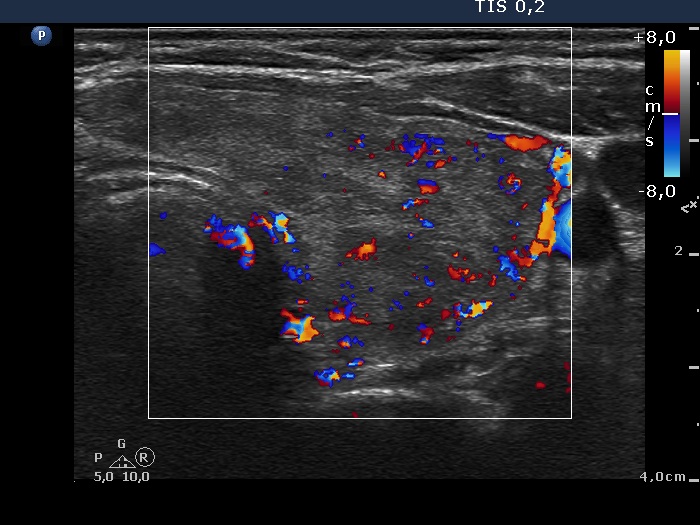

Consecutively operated patients with autoimmune thyroid disease - case 25 (419) (ultrasonographic picture 5)

Left lobe, transverse view, color Doppler mode. The vascularization is a bit increased.